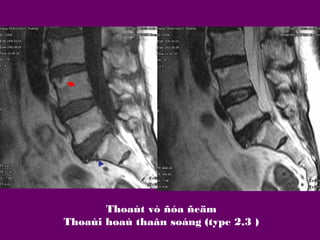

Thoaùt vò ñóa ñeäm

Thoaùi hoaù thaân soáng (type 1)

Thoaùi hoaù thaân soáng (type 2,3 )